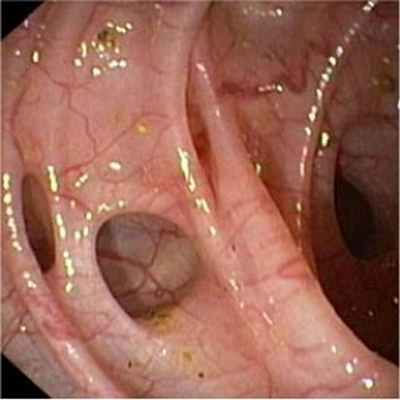

- Колоноскопия позволяет выявить наличие множественных дивертикулов, признаков воспаления или кишечного кровотечения, а также может оказаться полезной для обнаружения таких сопутствующих поражений как полипы и рак.

Основным диагностическим методом дивертикулярной болезни толстой кишки является фиброколоносокопия – внутрипросветный осмотр кишки, а также осмотр состояния слизистой у дивертикулов. Дополнительно может применяться ирригоскопия (осмотр на рентгенаппарате, после введения контрастного вещества в клизме). Также с целью уточнения применяются такие методы, как виртуальная фиброколоноскопия (когда осмотр проходит в аппарате МРТ, а компьютерная программа сама создает картинку кишечника в просвете).